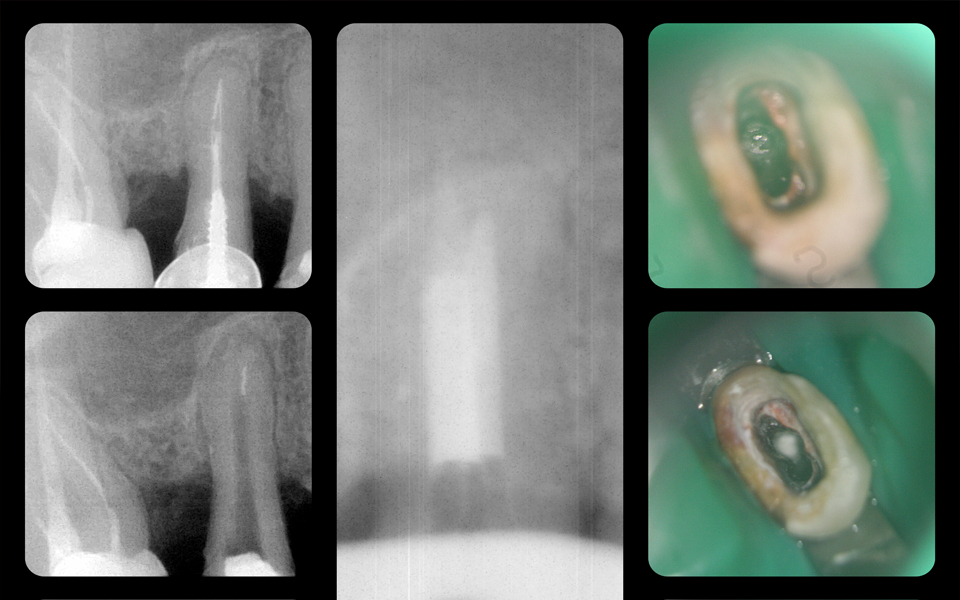

Перелечивание корневых каналов

Подробно